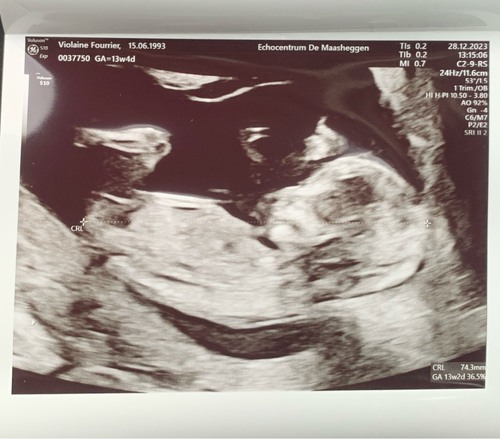

Echo met 12 weken, wat denken jullie? Met 11 weken dacht ik duidelijk een nub te zien wat dan een meisje zou zijn, maar deze zie ik het niet 🙈

Wat denken jullie. Een meisje of een jongetje in juli? Echo is 13+2 dagen � ...

Ik neig naar een jongen!